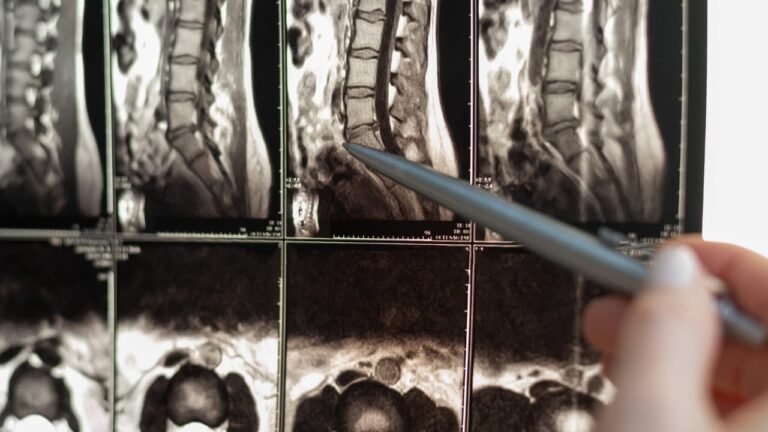

Em alguns casos, as neuropatias de aprisionamento surgem na coluna vertebral, como nas radiculopatias cervicais ou lombares. Estas condições ocorrem quando as raízes nervosas ficam comprimidas, muitas vezes devido a hérnias discais ou a alterações degenerativas na coluna vertebral. Embora estas doenças possam parecer distintas, partilham o mecanismo subjacente de compressão ou irritação do nervo, levando a uma variedade de sintomas sensoriais e motores.

Os meios de diagnóstico avançados, como a ressonância magnética e o eletrodiagnóstico, são ferramentas úteis para confirmar o diagnóstico em casos complexos. A ressonância magnética é útil para identificar alterações estruturais nos tecidos que provocam neuropatias, enquanto os estudos de condução nervosa podem avaliar o estado funcional dos nervos afectados. Este momento representa um desafio significativo, uma vez que as enxaquecas são predominantemente sentidas quando os indivíduos estão frequentemente concentrados nas suas carreiras, no trabalho e na educação dos filhos. Depois de atingirem este pico, muitas pessoas experimentam um declínio gradual na frequência das enxaquecas à medida que envelhecem, especialmente as mulheres, que podem notar uma redução nas ocorrências de enxaquecas por volta da menopausa.

O futuro do diagnóstico e tratamento da neuropatia de aprisionamento é promissor, graças aos avanços na imagiologia e na medicina de precisão. A RM de campo ultra-alto e a neurografia por RM estão a abrir caminho para diagnósticos mais precisos, permitindo aos médicos visualizar os nervos com um detalhe sem precedentes. Estas técnicas são particularmente valiosas para identificar alterações subtis na estrutura do nervo que podem não ser visíveis com a imagiologia tradicional.